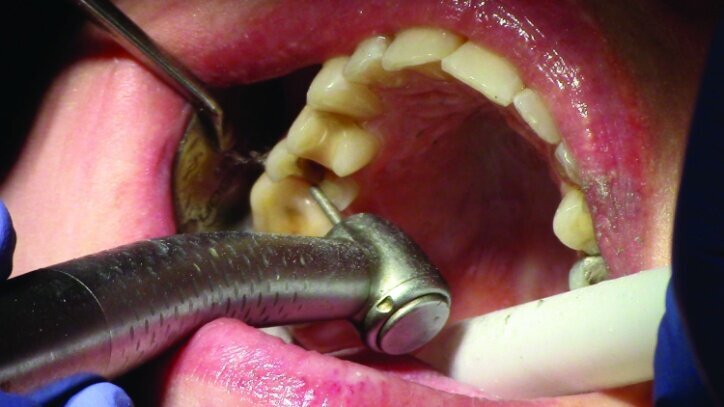

Gross occlusal reduction was completed using a KS7 bur to the depth cuts (Figs. 4–8b, 9c). Adequate clearance was verified with a 2 mm prep check from Common Sense Dental Products.

After gross occlusal reduction was completed, the remaining enamel ring was measured (Figs. 9a, b). The enamel rings were noted to be 1.5 mm, and the teeth were prepared for adhesively retained restorations. If the enamel rings were less than 1 mm, the teeth would have been prepared on the axial walls to create retention for cohesively retained crowns.